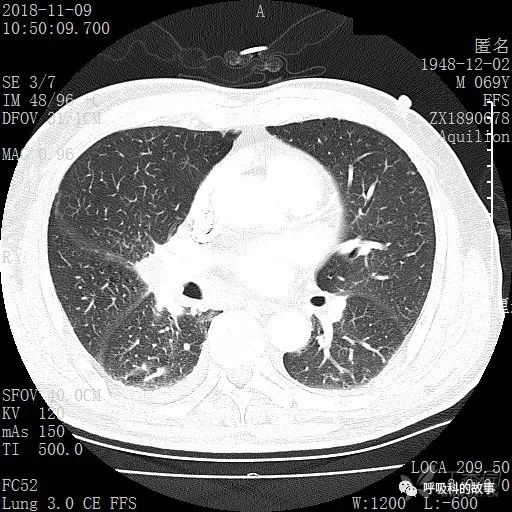

胸部增强CT示右肺门占位伴远端阻塞性肺炎,纵膈、右肺门、右侧颈根部、右侧腋下及肝门部肿大淋巴结。两侧胸腔少量积液。

纵隔窗的增强CT

肺窗CT